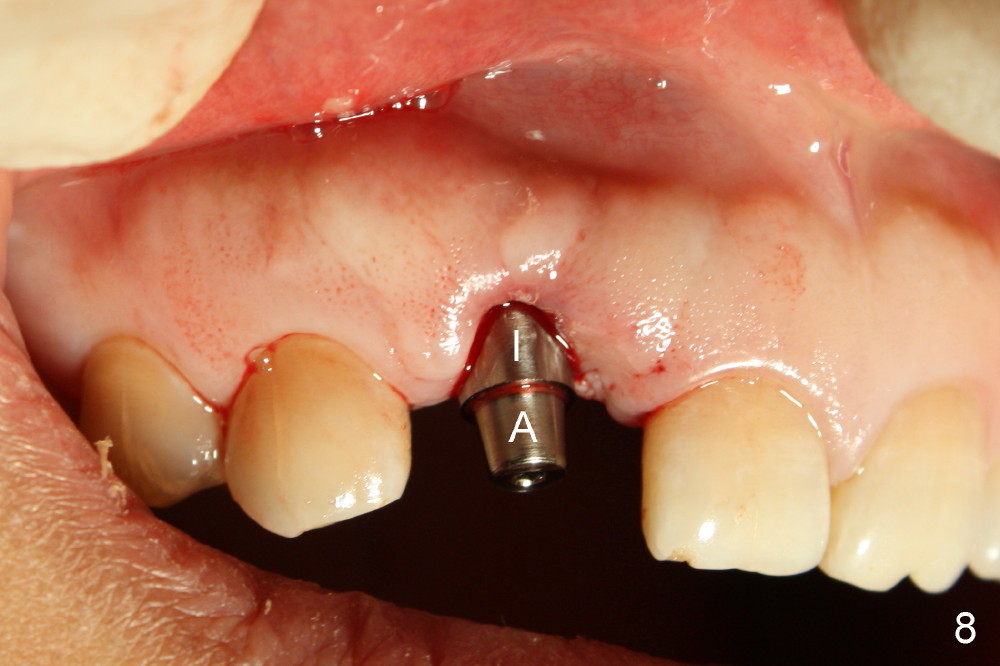

Malpositioned implant in the anterior region is cosmetically unacceptable. Immediate provisional allows us to note the issue immediately. The crown looks too long. Secondly, the provisional is easily dislodged, since the buccal aspect of the angled abutment is over trimmed (Fig.1). The implant (3.8x14 mm), which has been placed 3.5 months, is unexpectedly easily removed by reverse torque (Fig.2). The buccal wall is intact, whereas there seems to be enough bone lingually to place an implant. A small incision is made (Fig.11) so that the gingival tissue can be transferred buccally (Fig.12) and the immediate implant is to be placed palatally (Fig.13 white circle). There is no difficulty forming osteotomy in the palatal wall, followed by inserting 4.5x20 mm tap at the depth of 17 mm (Fig.3,5). But the tap is not palatal enough (Fig.4). By removing more palatal bone, the 4.5x17 implant (Fig.6) appears to be placed palatally enough for restoration (Fig.7; A: abutment; *: buccal gap). The biggest problem is that the palatal flap (Fig.7 arrowheads) cannot be pushed buccally; instead remains palatally. This leads to buccal tissue deficiency (Fig.8). Connective tissue graft is offered, but declined. The patient insists that she has low smile line. Following immediate provisional, mixture of allograft and synthetic graft is placed in the buccal gap (Fig.9). The overbuilt graft is held in place by perio dressing.